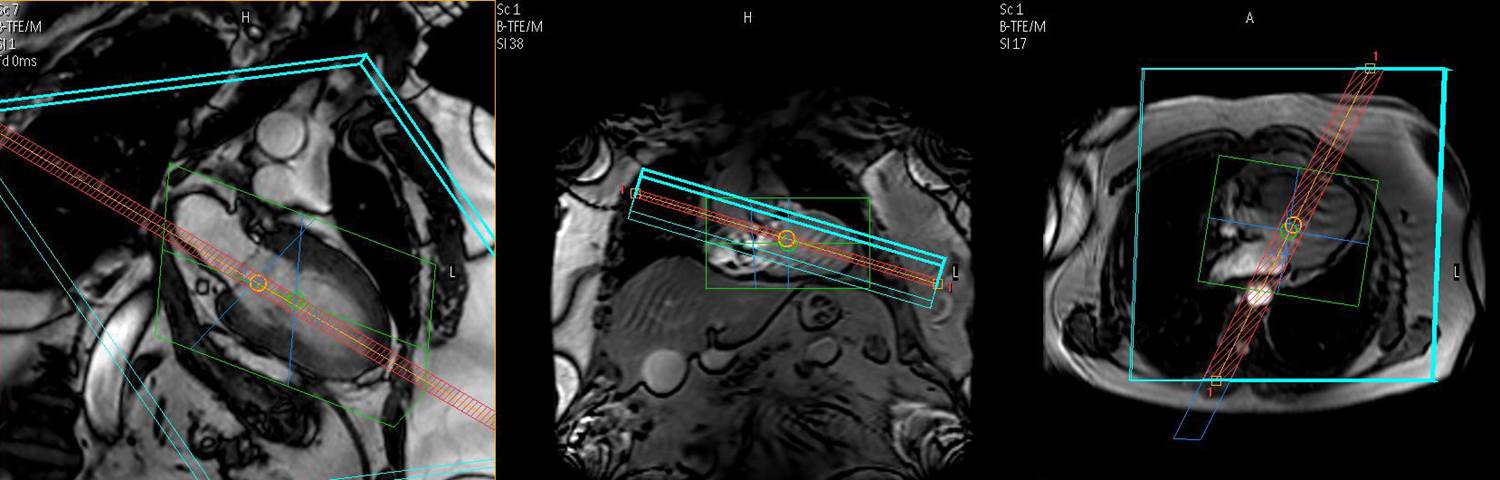

This course is designed for cardiologists and radiologists with at least 6 months of experience in clinical CMR. The main objective is to give an update on the clinically most important fields in CMR. There will be a particular emphasis on the principles and applications for quantitative tissue characterization using T1, T2, and T2* mapping techniques. The number of participants is limited and there will be plenty of opportunities to read and interpret CMR cases using dedicated CMR software. Cases interpreted during this workshop will be kept in a logbook and may be used for certification purposes.